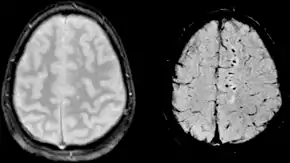

Diffusion weighted imaging offers a powerful means to detect acute stroke. Although it is well known that gradient echo imaging can detect hemorrhage, it is best detected with SWI. In the example shown here, the gradient echo image shows the region of likely cytotoxic edema whereas the SW image shows the likely localization of the stroke and the vascular territory affected (data acquired at 1.5 T).

The bright region in the gradient echo weighted image shows the area affected in this acute stroke example. The arrows in the SWI image may show the tissue at risk that has been affected by the stroke (A, B, C) and the location of the stroke itself (D). The reason that we are able to see the affected vascular territory could be because there is a reduced level of oxygen saturation in this tissue, suggesting that the flow to this region of the brain could be reduced post stroke. Another possible explanation is that there is an increase in local venous blood volume. In either case, this image suggests that the tissue associated with this vascular territory could be tissue at risk. Future stroke research will involve comparisons of perfusion weighted imaging and SWI to learn more about local flow and oxygen saturation.